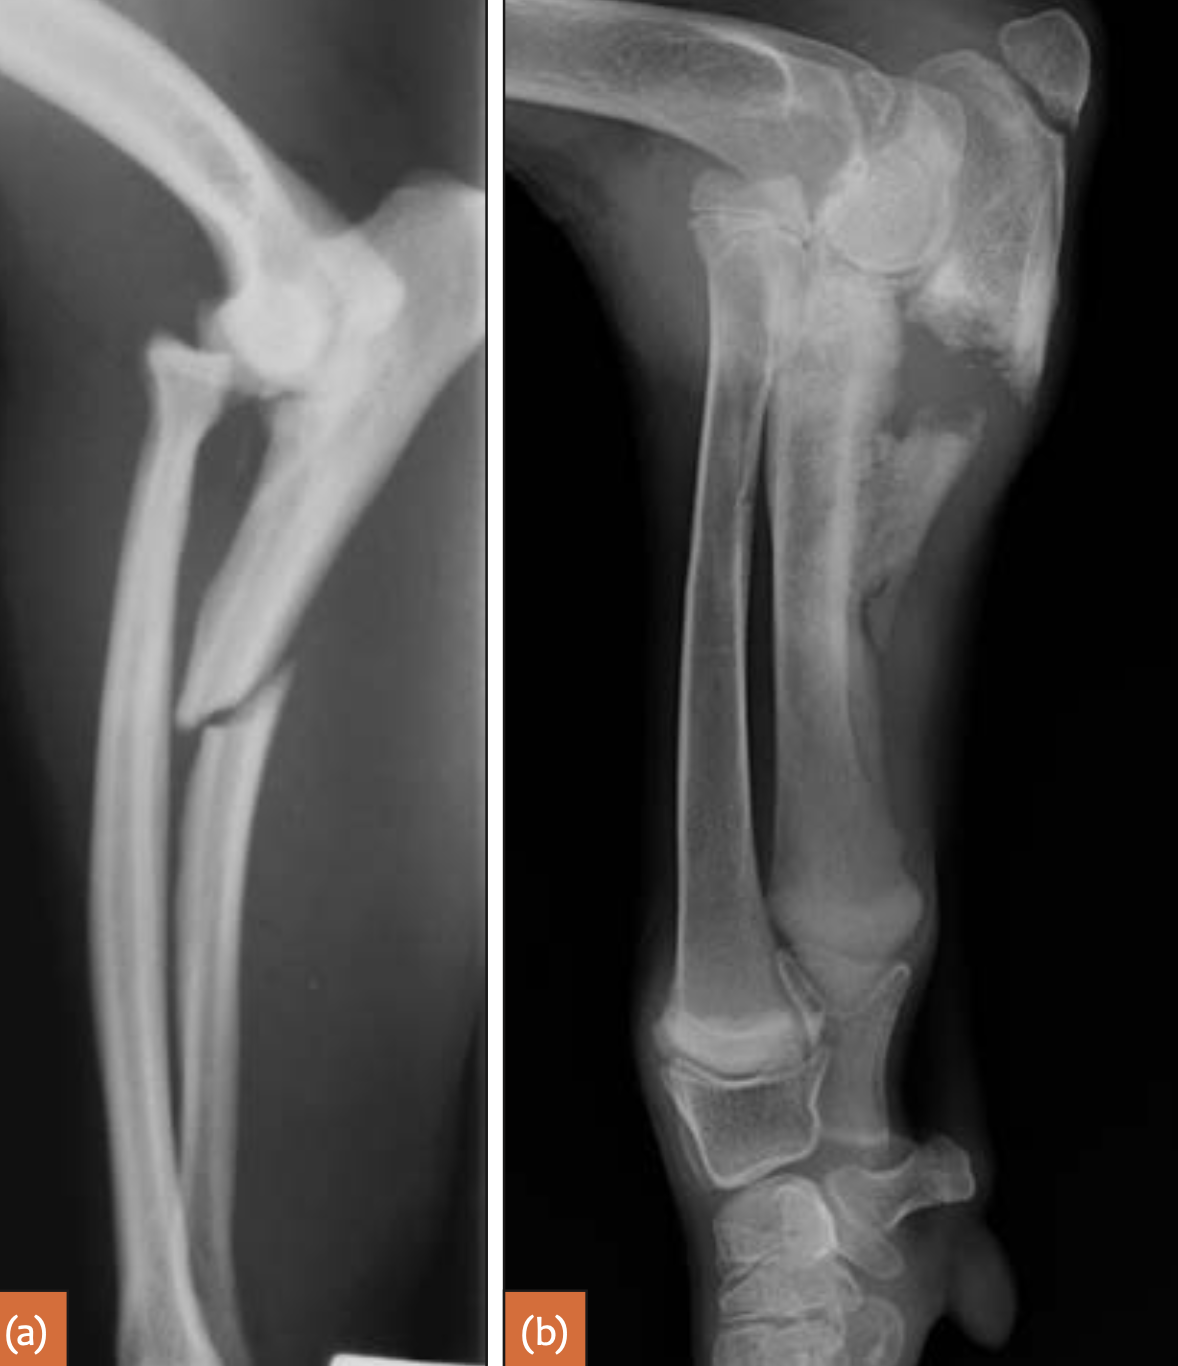

What is a Monteggia fracture?

Proximal ulnar fracture (articular or non-articular) accompanied by a cranial luxation of the proximal radius and distal ulnar fragment

Q

Monteggia fractures